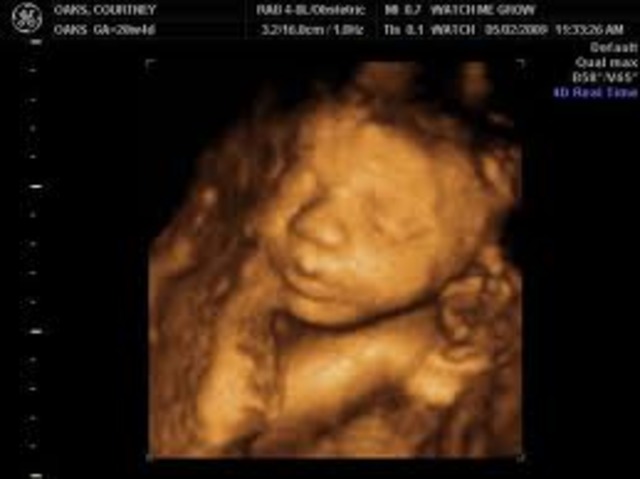

• Month 5- Baby

Month 5- Baby

The size of the baby is about 6 1/2 -7 in. (16-18cm) long. About 4-5 oz. (113-142g). Hair, eyelashes, and eyebrow's appear. Teeth continue to develope. Organs are maturing. Becomes more active.